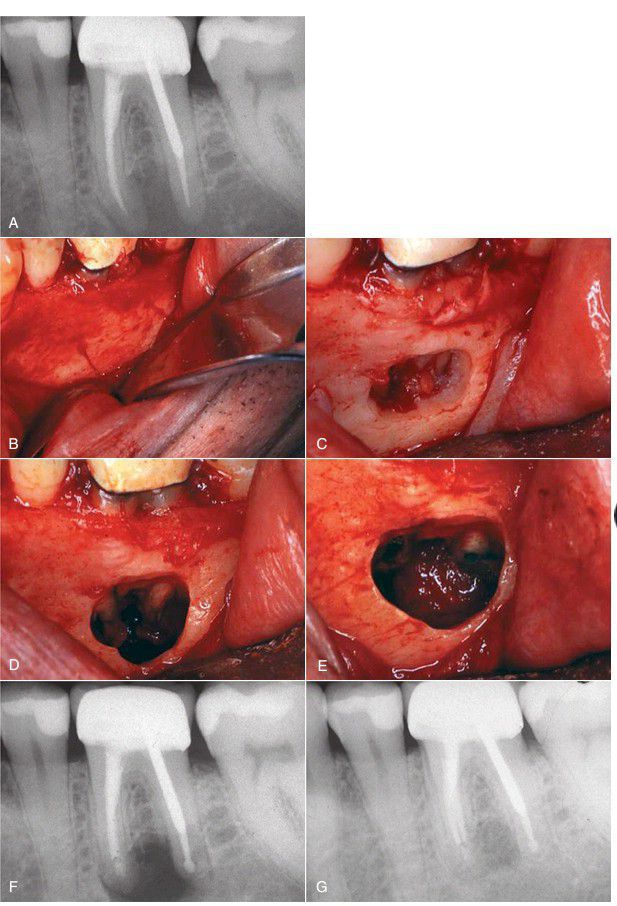

A preoperative radiograph showing the periapical pathologic condition amenable to apical surgery. (B) Full-thickness mucoperiosteal flap to expose lateral border of mandible. As is typical, no obvious bony perforation exists. (C) Careful removal of the thick buccal bone to expose the apical portion. (D) Apical one-third exposed before resection of root. (E) Both roots resected and mineral trioxide aggregate seal placed following ultrasonic preparation. (F) Immediate postoperative radiograph with mineral trioxide aggregate seal visible. (G) Five months after surgery, bone fill is evident.